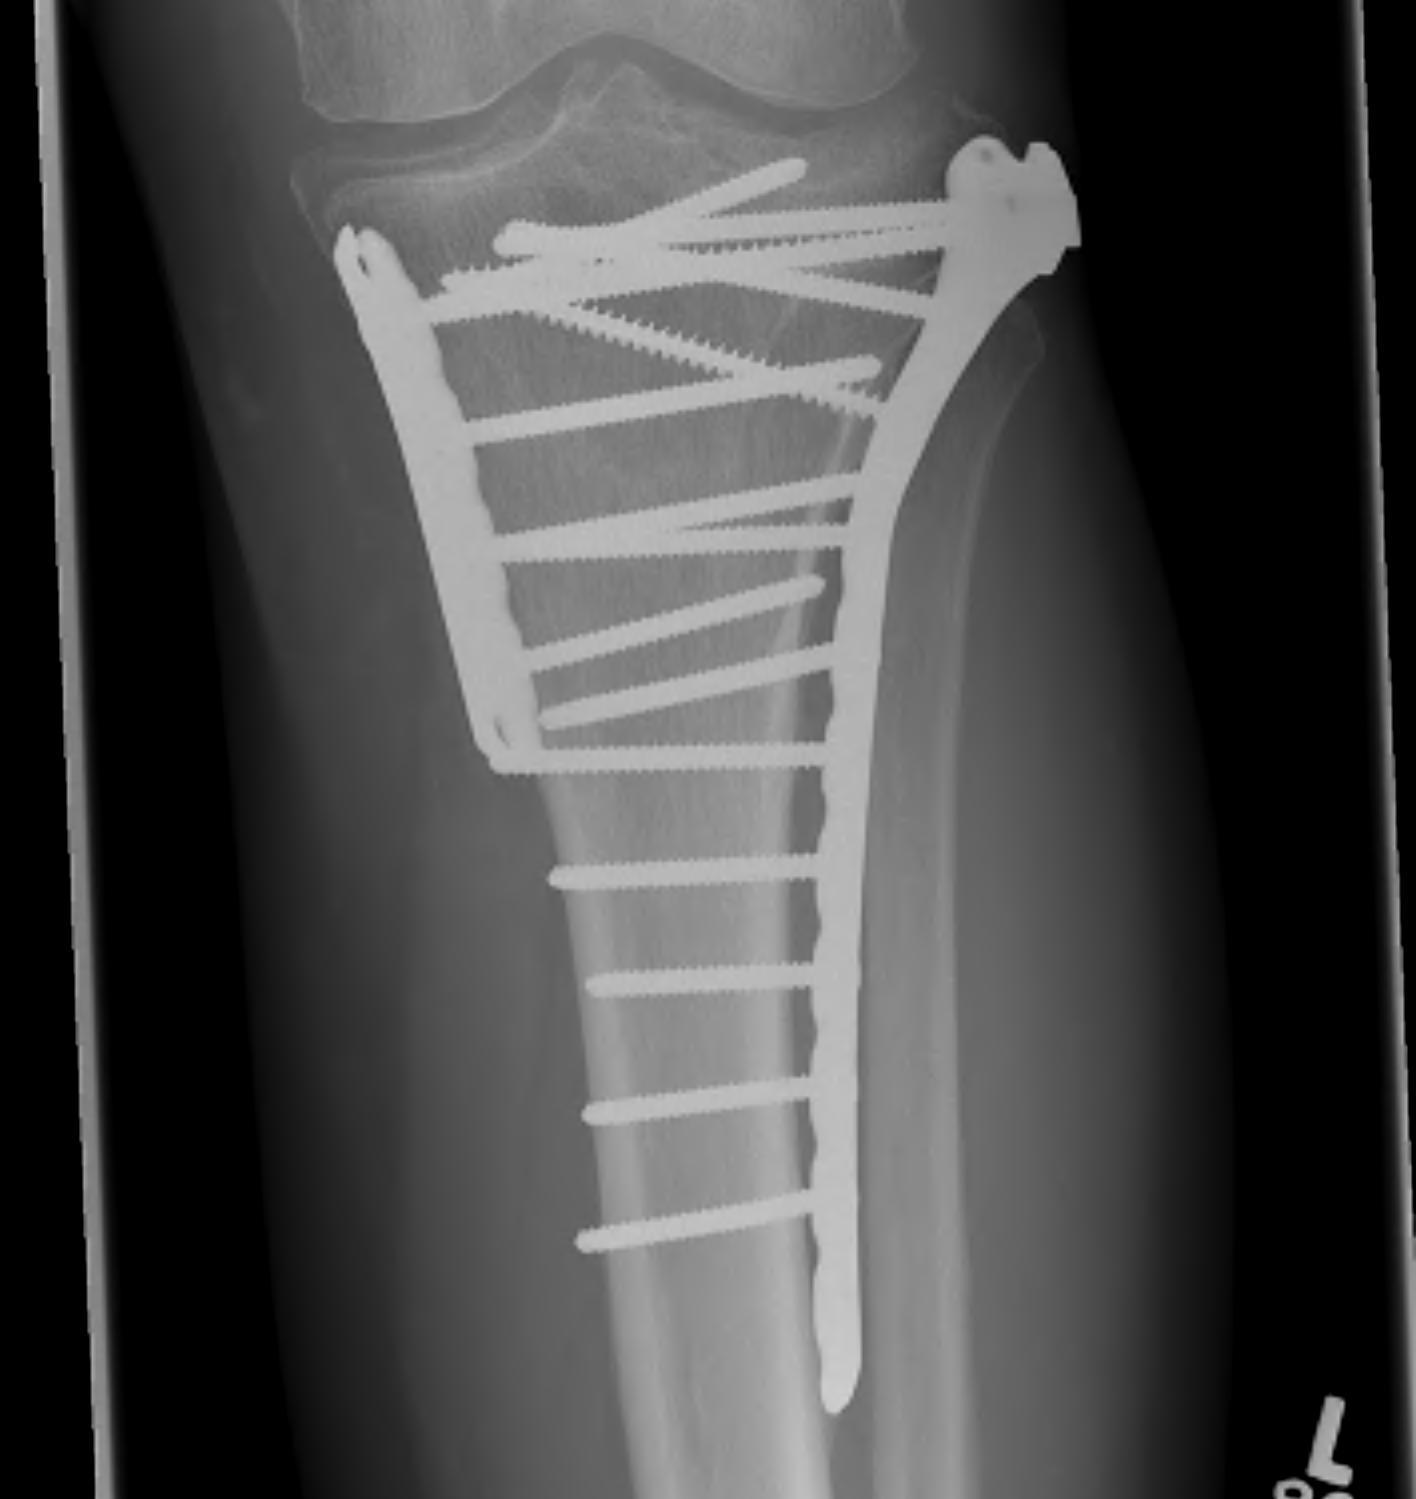

1. Medial and Lateral Plating

Technique

- depends on which of the three columns affected

- anterolateral approach for lateral column

- posteromedial appraoch for medial / posterior column